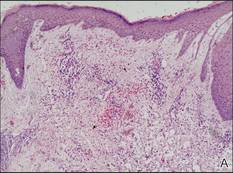

Figure 3. Skin biopsy revealed granulomatous and gelatinous tissue reaction with ovoid encapsulated spores (A)(H&E, original magnification ×40). Ovoid, budding, encapsulated spores of Cryptococcus were seen on higher power (B)(H&E, original magnification ×400). |

Gram stain and a potassium hydroxide (KOH) mount of a smear from the ulcerated lesion on the neck showed encapsulated budding spores. Histopathologic study of hematoxylin and eosin–stained sections from the noduloulcerative lesion on the shoulder demonstrated irregular acanthosis in the epidermis; a granulomatous reaction comprised of lymphocytes, histiocytes, neutrophils, plasma cells, and few giant cells; and a gelatinous tissue reaction with numerous ovoid encapsulated spores (Figure 3). Gomori methenamine-silver stain revealed black-colored, ovoid, budding spores (Figure 4), and periodic acid–Schiff stain also revealed narrow-based budding spores. Mucicarmine staining showed multiple red-colored, budding, capsulated spores (Figure 5). A culture on Sabouraud dextrose agar confirmed growth of C neoformans. Examination of sputum by KOH mount and india ink preparation demonstrated encapsulated spores of Cryptococcus. India ink staining of cerebrospinal fluid and urine was negative for Cryptococcus. Cerebrospinal fluid cytochemistry was within reference range. The final diagnosis was disseminated cryptococcosis in the setting of uncontrolled DM.